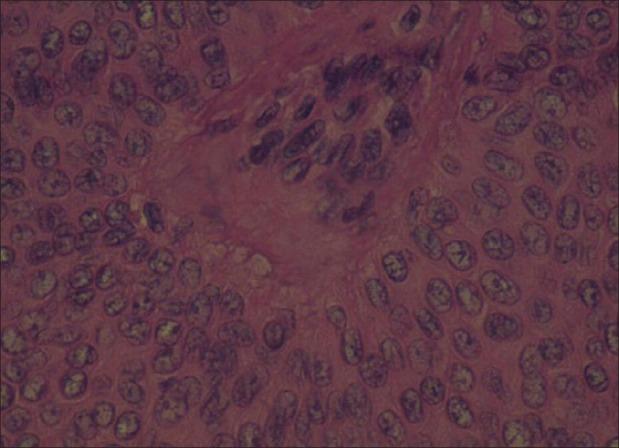

An eccrine poroma is a solitary tumor arising from the eccrine duct epithelium in the epidermis. The lesions commonly occur on the sole of the foot, the hands, and occasionally on the nose, eyelids, neck, and chest. We report a patient who presented with a slow-growing nodular lesion over her left cheek, prompting a diagnosis of basal cell carcinoma or keratoacanthoma. Biopsy from the nodule revealed a well-defined epidermal tumor with uniform small cuboidal cells with rounded deeply basophilic nuclei, few narrow ductal lumina, and occasional cystic spaces confirming the diagnosis of an eccrine poroma.

小汗腺汗孔瘤是一种起源于表皮内小汗腺导管上皮的孤立性肿瘤。病变通常发生在足底、手部,偶尔也出现在鼻子、眼睑、颈部和胸部。我们报告了一名患者,其左脸颊出现一个生长缓慢的结节性病变,最初诊断为基底细胞癌或角化棘皮瘤。对该结节进行活检,发现一个边界清晰的表皮肿瘤,由均匀的小立方形细胞组成,细胞核圆形、深嗜碱性,有少量狭窄的导管腔,偶尔可见囊性间隙,确诊为小汗腺汗孔瘤。